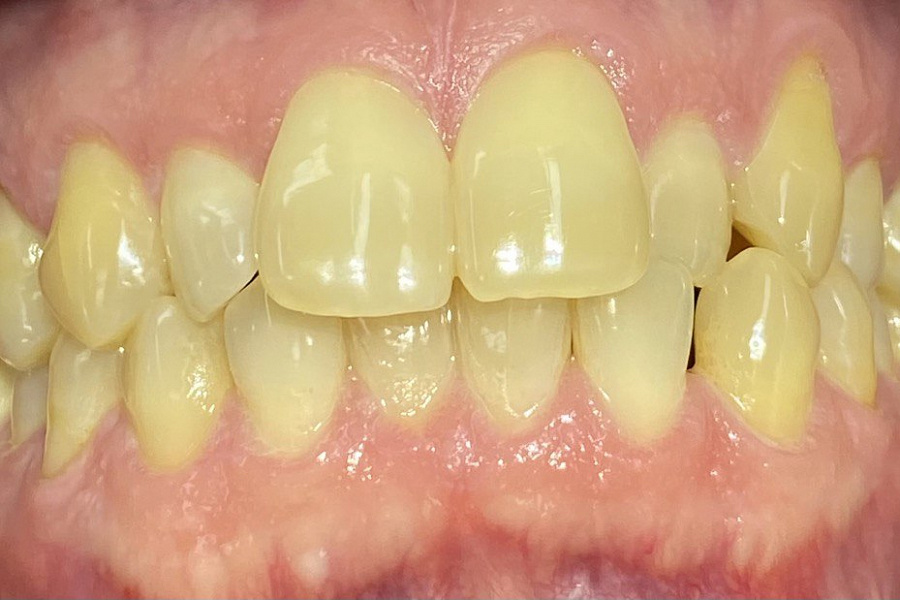

Ортодонтическое лечение с помощью элайнеров длилось 10 месяцев. Далее последовало протезирование и установка виниров.

Результат лечения